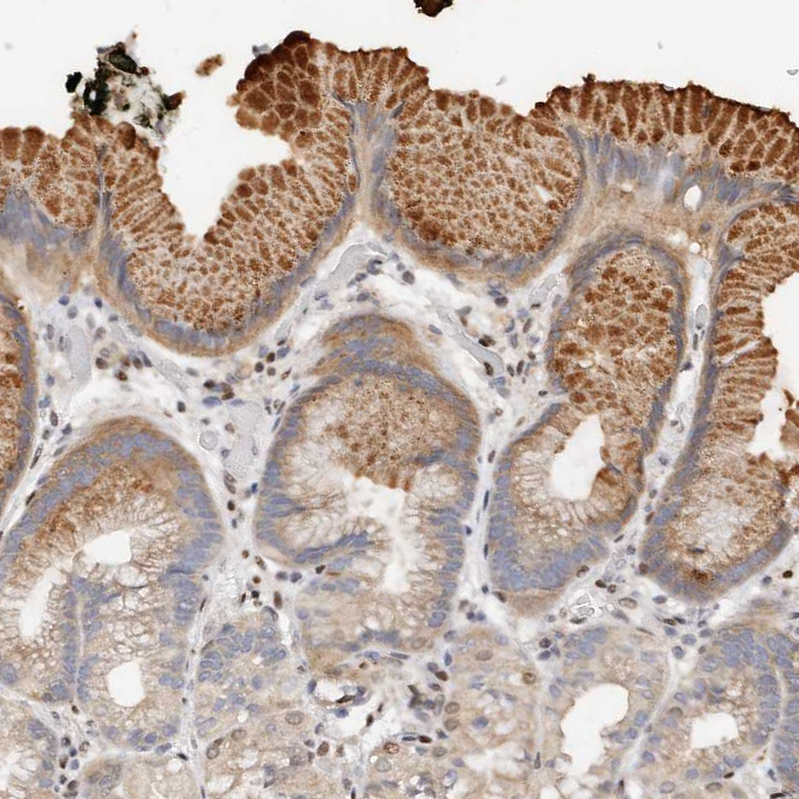

Immunohistochemical staining of human duodenum shows moderate cytoplasmic positivity in glandular cells.